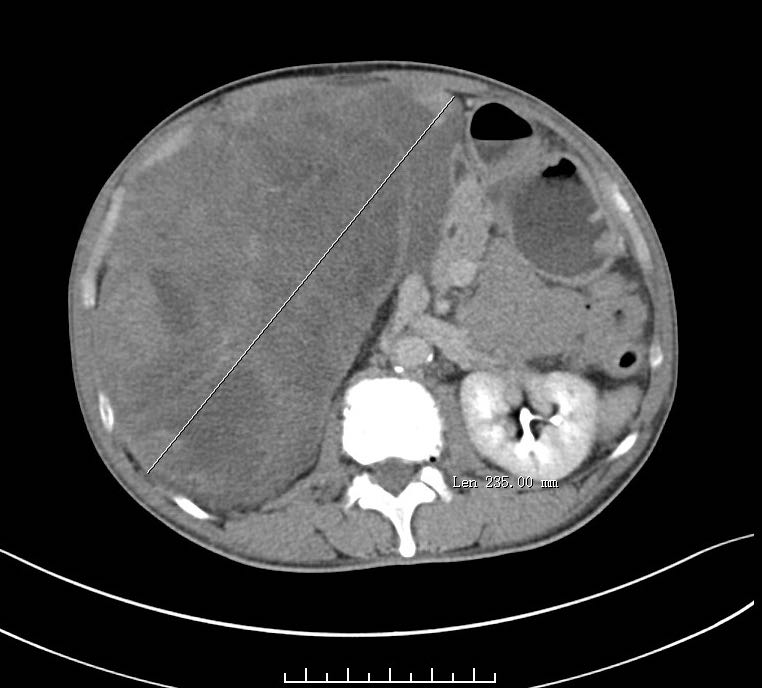

术前CT检查提示,老人体内有巨大的腹膜后肿瘤。 本文图片均为 上海市杨浦区中心医院 供图

3月11日,澎湃新闻记者从接诊老人的上海市杨浦区中心医院获悉,这名老人进入医院普外科就诊后发现,其腹部隆起有肿块,犹如篮球般大小。经CT检查显示,老人体内巨大的腹膜后肿瘤占据了大半个腹盆腔,小肠、结肠已被推挤至左侧腹腔一角,并且肿瘤紧贴右肾、肾动脉、下腔静脉及十二指肠,分界都不是很清楚了。

术后,经测量,切除的肿瘤大小为44.5x23.5厘米,足足重达5千克。